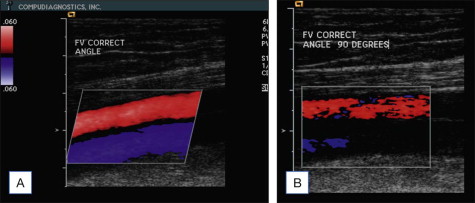

Color flow indicates presence, direction and relative magnitude of movement. In particular, when applied to the movement of blood or blood velocity, flow is displayed as a color pixel. The concept of movement detection, however, must be kept in the mind of the ultrasound user since transducer movement or vessel movement may be interpreted erroneously as blood flow. The display of the upper and lower segments of the color bar ( Fig. 4.1A ) serve as a reference to indicate flow direction, or movement, either toward or away from the transducer. Longitudinal images of vessels in axial positions commonly depict arteries in red (flow away from the heart) and veins in blue (flow towards the heart) ( Fig. 4.1A ). With this setting, red pixels inside the vein represent reverse flow. Color images can be displayed in longitudinal or transverse images. The transverse, oblique image facilitates (1) simultaneous visualization of multiple veins, and (2) assessment of diameter measurements. The standard documentation of reflux has been accepted to be displayed in a longitudinal format combined with Doppler spectral tracings.

Color flow sensitivity is dependent on flow physics and is controlled by instrument settings. Velocity, blood volume and direction affect detection of color flow. Difficulties in detecting low velocity are well recognized. Flow directly toward or away from the transducer, representing an angle of insonation equal to zero, produces the highest sensitivity. An angle of insonation of approximately 60° is commonly employed to longitudinally image vessels parallel to the skin ( Fig. 4.1A ). Flow parallel to the transducer, representing an angle of insonation of 90°, results in lowest sensitivity ( Fig. 4.1B ). The three-dimensional images are displayed on a viewing monitor in a two-dimensional formatted image, which visually can create confusion for the untrained user.